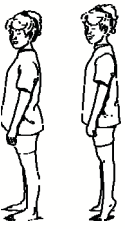

Ενδυνάμωση του γόνατος ενώ στέκεστε και κάμψη του ενός γόνατος

Σταθείτε ευθυτενείς στο πόδι που πονάει στην άκρη ενός σκαλιού και χρησιμοποιήστε μια καρέκλα για να στηρίζεστε. Λυγίστε το πονεμένο πόδι σας και σιγά-σιγά χαμηλώστε το άλλο πόδι κάτω από το ύψος του σκαλιού. Κανονικά πρέπει να αισθανθείτε ένα ελαφρύ τέντωμα στους μυς του γόνατός σας. Το χαμήλωμα πρέπει να διαρκέσει 3-5 δευτερόλεπτα. Το γόνατό σας πρέπει να είναι στραμμένο μπροστά.

Παραμείνετε σε αυτή τη θέση για 2 δευτερόλεπτα και επαναλάβετε την άσκηση 10-15 φορές 2 φορές την ημέρα. Με τις παραπάνω μεθόδους θα ανακουφιστείτε από τον πόνο στο γόνατο!

Ασκήσεις με βάρος Δοκιμάστε αυτές τις ασκήσεις όσο σας το επιτρέπει ο πόνος, μία εβδομάδα περίπου μετά τον τραυματισμό Σηκωθείτε στις μύτες των ποδιών σας. Επαναλάβετε 10 φορές, 3 φορές ημερησίως.